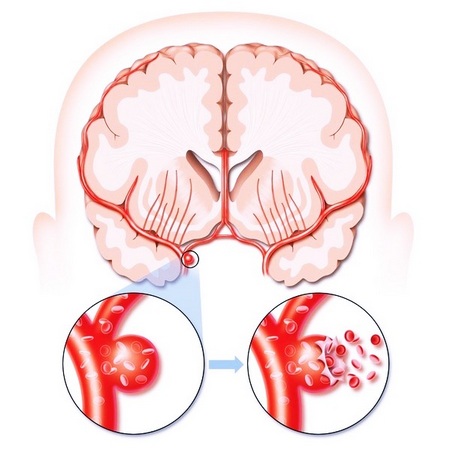

- Может также возникать разрыв сосуда. Кровь изливается в ткани/оболочки мозга. Это геморрагический инсульт.

От чего бывает инсульт геморрагический? Причины геморрагического инсульта – аневризмы, гипертония.

При кровоизлиянии артерия мозга просто разрывается. От такого инсульта можно пострадать в любом возрасте.

Основные причины кровоизлияния:

- высокое давление;

- диабет;

- аритмия;

- патологически плотные артерии;

- резкое повышение давления;

- неактивный образ жизни;

- оральные контрацептивы;

- стресс, паническая атака;

- курение.